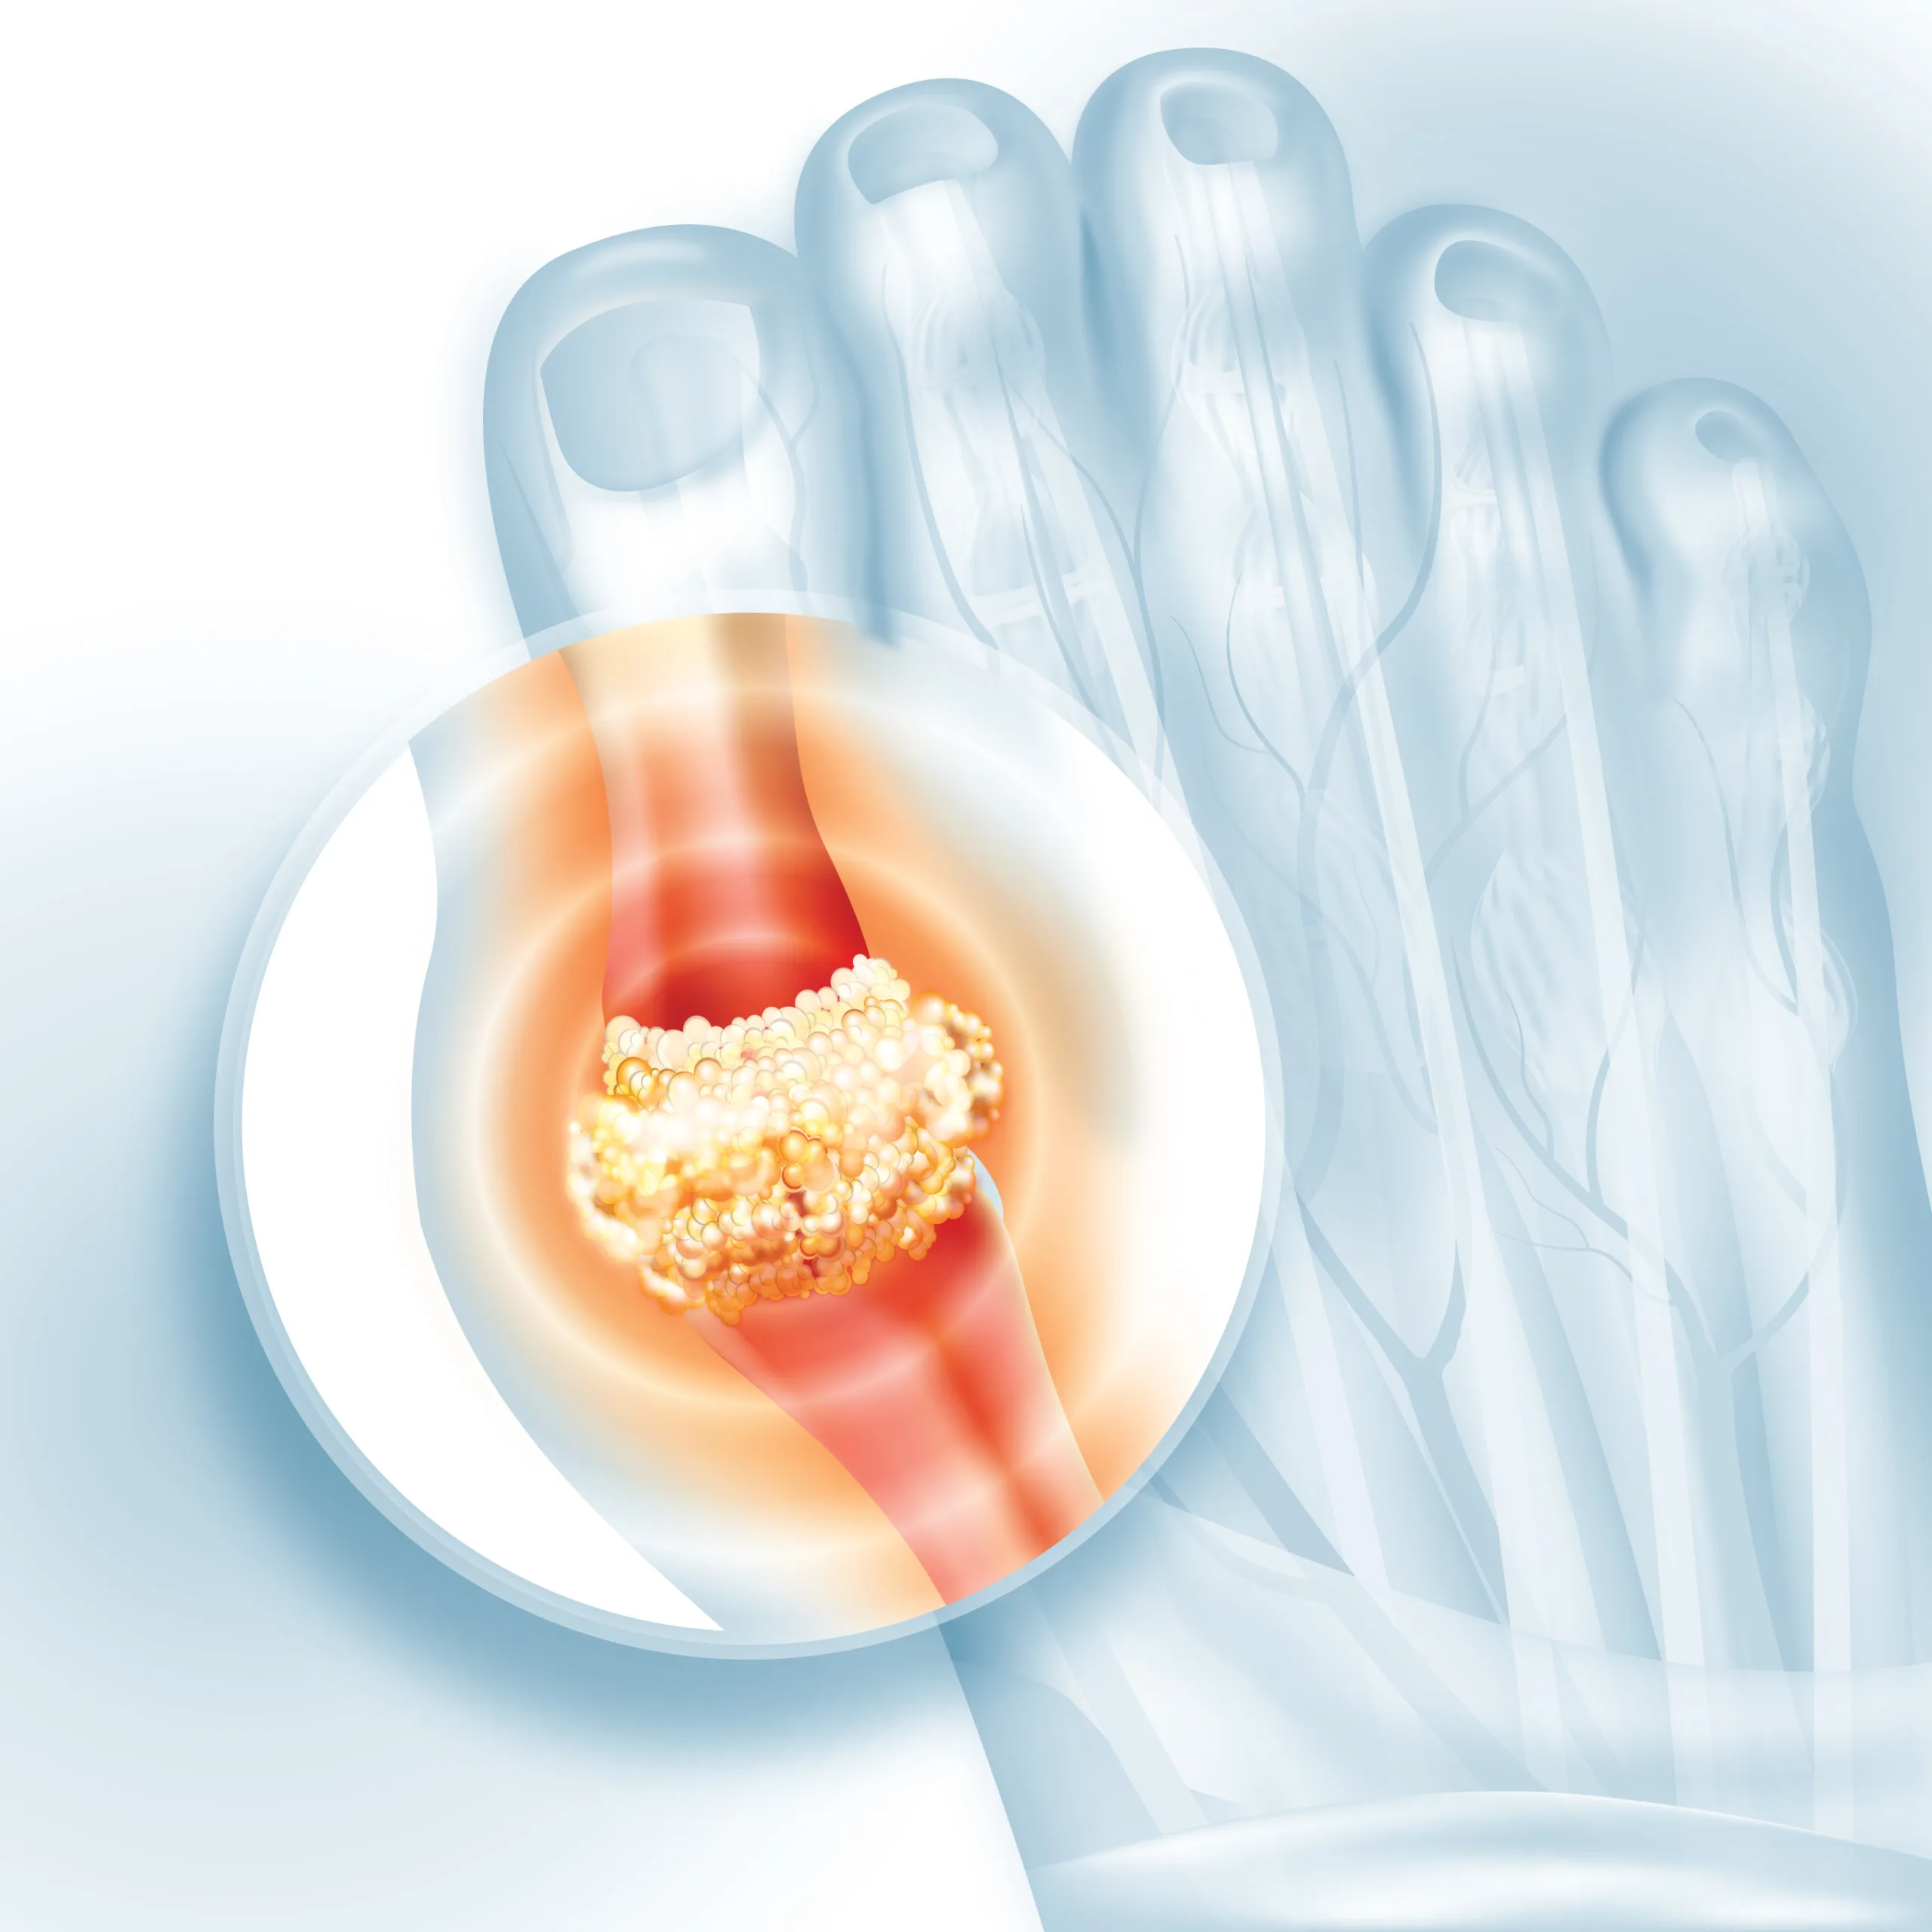

यूरिक एसिड शरीर का एक अपशिष्ट पदार्थ है. यह तब बनता है जब शरीर ‘प्यूरीन’ नाम के केमिकल को तोड़ता है, ये केमिकल हमारे भोजन में पाए जाते हैं. आमतौर पर, विशेषज्ञ बताते हैं कि यूरिक एसिड ब्लड फ्लो में घुल जाता है और किडनी द्वारा फिल्टर किया जाता है, जिसके बाद यह पेशाब के माध्यम से शरीर से बाहर निकल जाता है. हालांकि, विशेषज्ञ यह भी बताते हैं कि जब इसका लेवल बहुत ज्यादा बढ़ जाता है या जब किडनी इसे प्रभावी ढंग से बाहर निकालने में असमर्थ होते हैं, तब यूरिक एसिड शरीर के भीतर जमा होना शुरू हो जाता है. और बाद में, यह जोड़ों और ऊतकों के आसपास सुई जैसे क्रिस्टल बना लेता है, जिससे सूजन, दर्द और गठिया जैसी गंभीर समस्याएं उत्पन्न हो सकती हैं.

नेशनल इंस्टीट्यूट ऑफ हेल्थ के एक अध्ययन के अनुसार, अगर आपकी किडनी ठीक से काम नहीं कर रही हैं, तो समझ लें कि खून में यूरिक एसिड का स्तर बढ़ गया है. इस स्थिति को ‘हाइपरयूरिसीमिया’ कहा जाता है. यूरिक एसिड शरीर में कहीं भी जमा हो सकता है. लेकिन, विशेषज्ञ बताते हैं कि यह मुख्य रूप से जोड़ों और किडनी के आसपास जमा होता है. विशेषज्ञों का मानना है कि शरीर में यूरिक एसिड का बढ़ा हुआ लेवल हार्ट डिजीज, डायबिटीज और किडनी से जुड़ी समस्याओं का खतरा बढ़ा सकता है.

- हाइपरयूरिसीमिया से पीड़ित लोगों को अपने जोड़ों, पैरों और टांगों में सूजन और असहनीय दर्द का अनुभव होता है.

- कुछ लोगों को अपने पैरों के तलवों में जलन का भी अनुभव होता है. इसके अलावा, पैर के बड़े अंगूठे में भी दर्द हो सकता है.